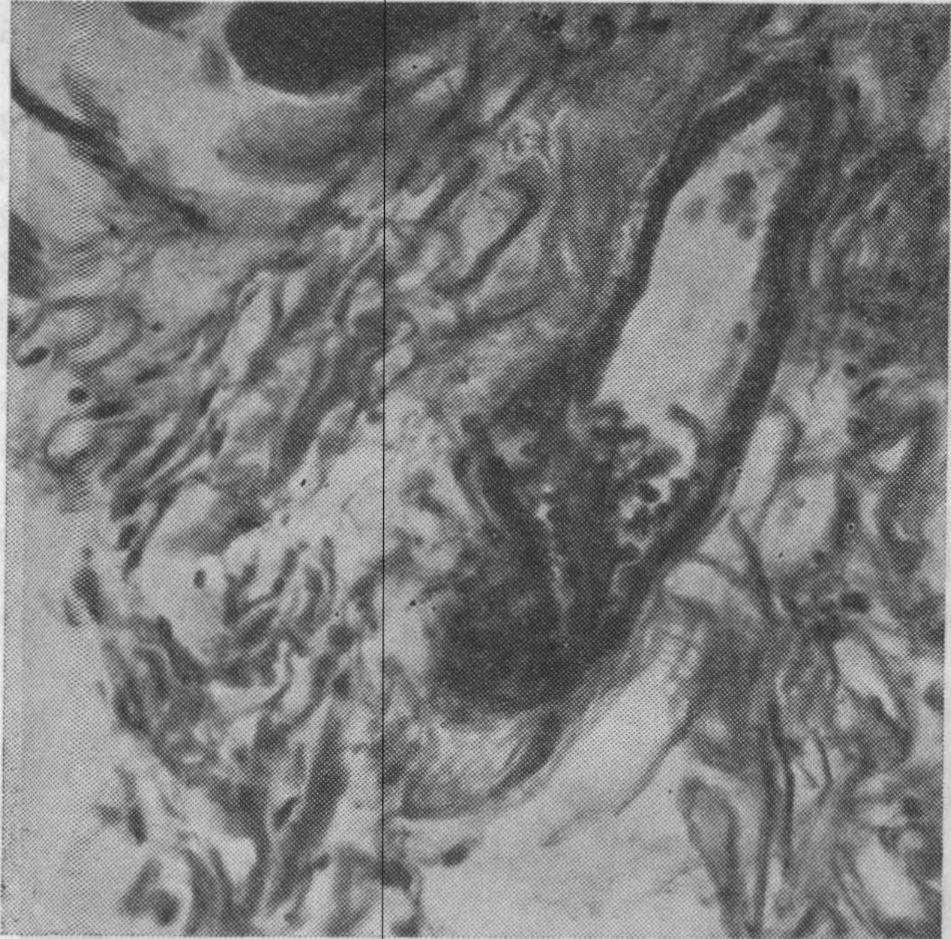

Микроскопическое исследование гистологических препаратов собственно жевательной мышцы собаки, окрашенных гематоксилин-эозином, пикрофуксином по ВанГизону, на гликоген, по Шабадашу, импрегнированных нитратом серебра по Футу и по Бильшовскому — Грос, через различные сроки после повышения высоты прикуса на 14 мм показало, что в ответ на растяжение мышцы в последней выявляется комплекс морфологических изменений. Уже на 2-е сутки ясно выступает функциональное напряжение мышц в виде утолщения волокон, набухания саркоплазмы, в которой наблюдается неравномерное распределение гликогена. Кроме того, отмечались спастическое состояние артерий, набухание стенок мелких кровеносных сосудов, стаз, перикапиллярный отек. В моторных и чувствительных нервных аппаратах жевательной мышцы явления раздражения проявляются в виде неравномерного утолщения нервных волокон, по ходу которых иногда отмечаются колбовидные утолщения и шаровидные вздутия. Часто в нервных пучках, представленных мякотными и безмякотными волокнами, отмечались распад миелиновой оболочки и нейроплазмы, фрагментация осевых цилиндров (рис. 58). На 7-е сутки, кроме того, в мышечных волокнах обнаруживали иногда изменения

Рис. 58. Собственно жевательная мышца собаки через 7 сут от начала опыта. Нервные волокна вплетаются в толщу сарколеммы, некоторые из них имеют на концах пуговчатые утолщения. Четко выявляются неравномерно утолщенные нервные волокна с повышенной аргирофилыюстыо.

Импрегнация серебром по Бильшовскому—Грос. Х280 (Кондратов В. А.).